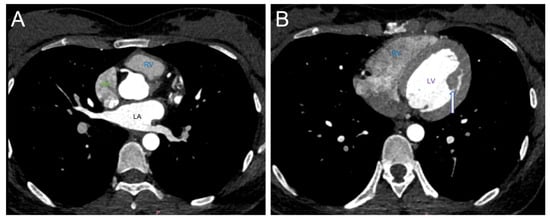

2. Case Report